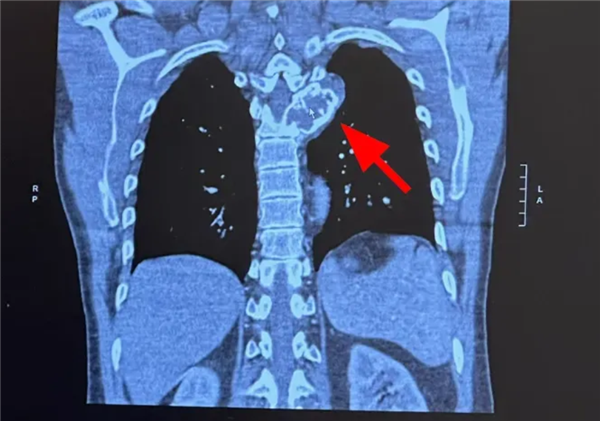

AI技术对海量医学文献、基因数据及病灶信息进行高效分析,精准识别出了FAP成纤维细胞活化蛋白这一关键治疗靶点,还及时纠正了肺部病灶的误诊问题。

基于AI锁定的治疗靶点,西德在德国接受了镥- 177放射配体疗法。

经过两次治疗,其体内肿瘤坏死率达到60%,肿瘤体积缩小20%,同时体内杀伤性T细胞占比从19%提升至89%。